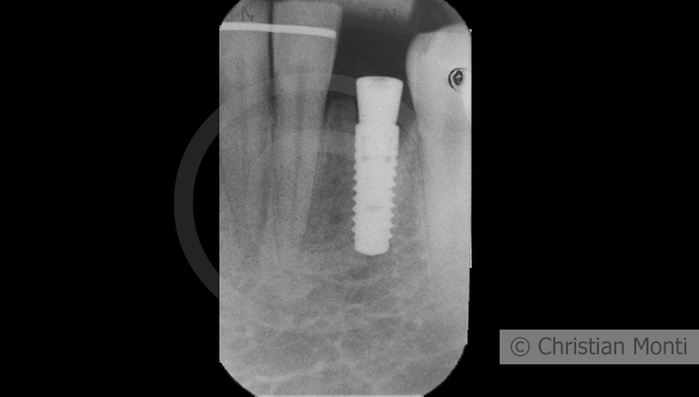

EDENTULIA SINGOLA

Impianto in sostituzione di un canino deciduo